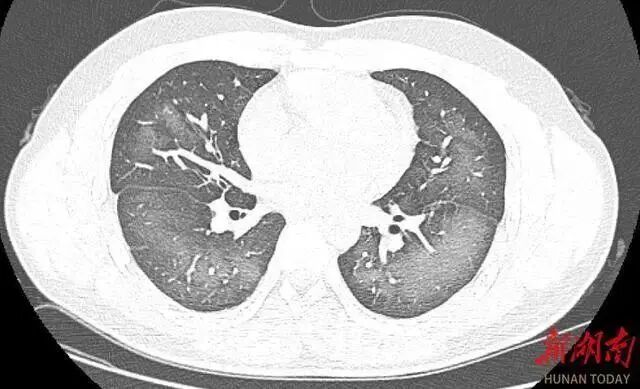

经检查,肺部CT片显示,李林双肺赫然呈现大范围白色样病变,报告提示“白肺”。

“白肺”一般是指重症肺炎在X线或CT检查下的表现,患者肺部呈现一大片的白色状态,往往会出现呼吸困难、呼吸衰竭,严重者还会出现其他脏器功能障碍。

长沙市第三医院放射影像科的接诊医师表示,除了感染、弥漫性肺泡出血综合征等“白肺”最常见的病因外,吸入有害物质如粉尘、喷雾等,也可导致肺部出现大范围白色样病变。这位年轻的患者就是因为使用不当,吸入了一部分防晒产品进入肺部,导致“白肺”的发生。